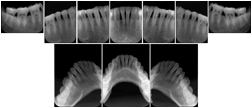

2. A patient requests cosmetic surgery to enhance their facial appearance. The case requires consultation between an orthodontist in New York and an oral surgeon in California. The cephalometric series of 2D projections constructed from a volumetric CT data set that is used for the discussion is arranged by a Structured Display for transfer between the two practitioners.

Cephalometric Series Structured Display

Figure OO-2. Cephalometric Series Structured Display